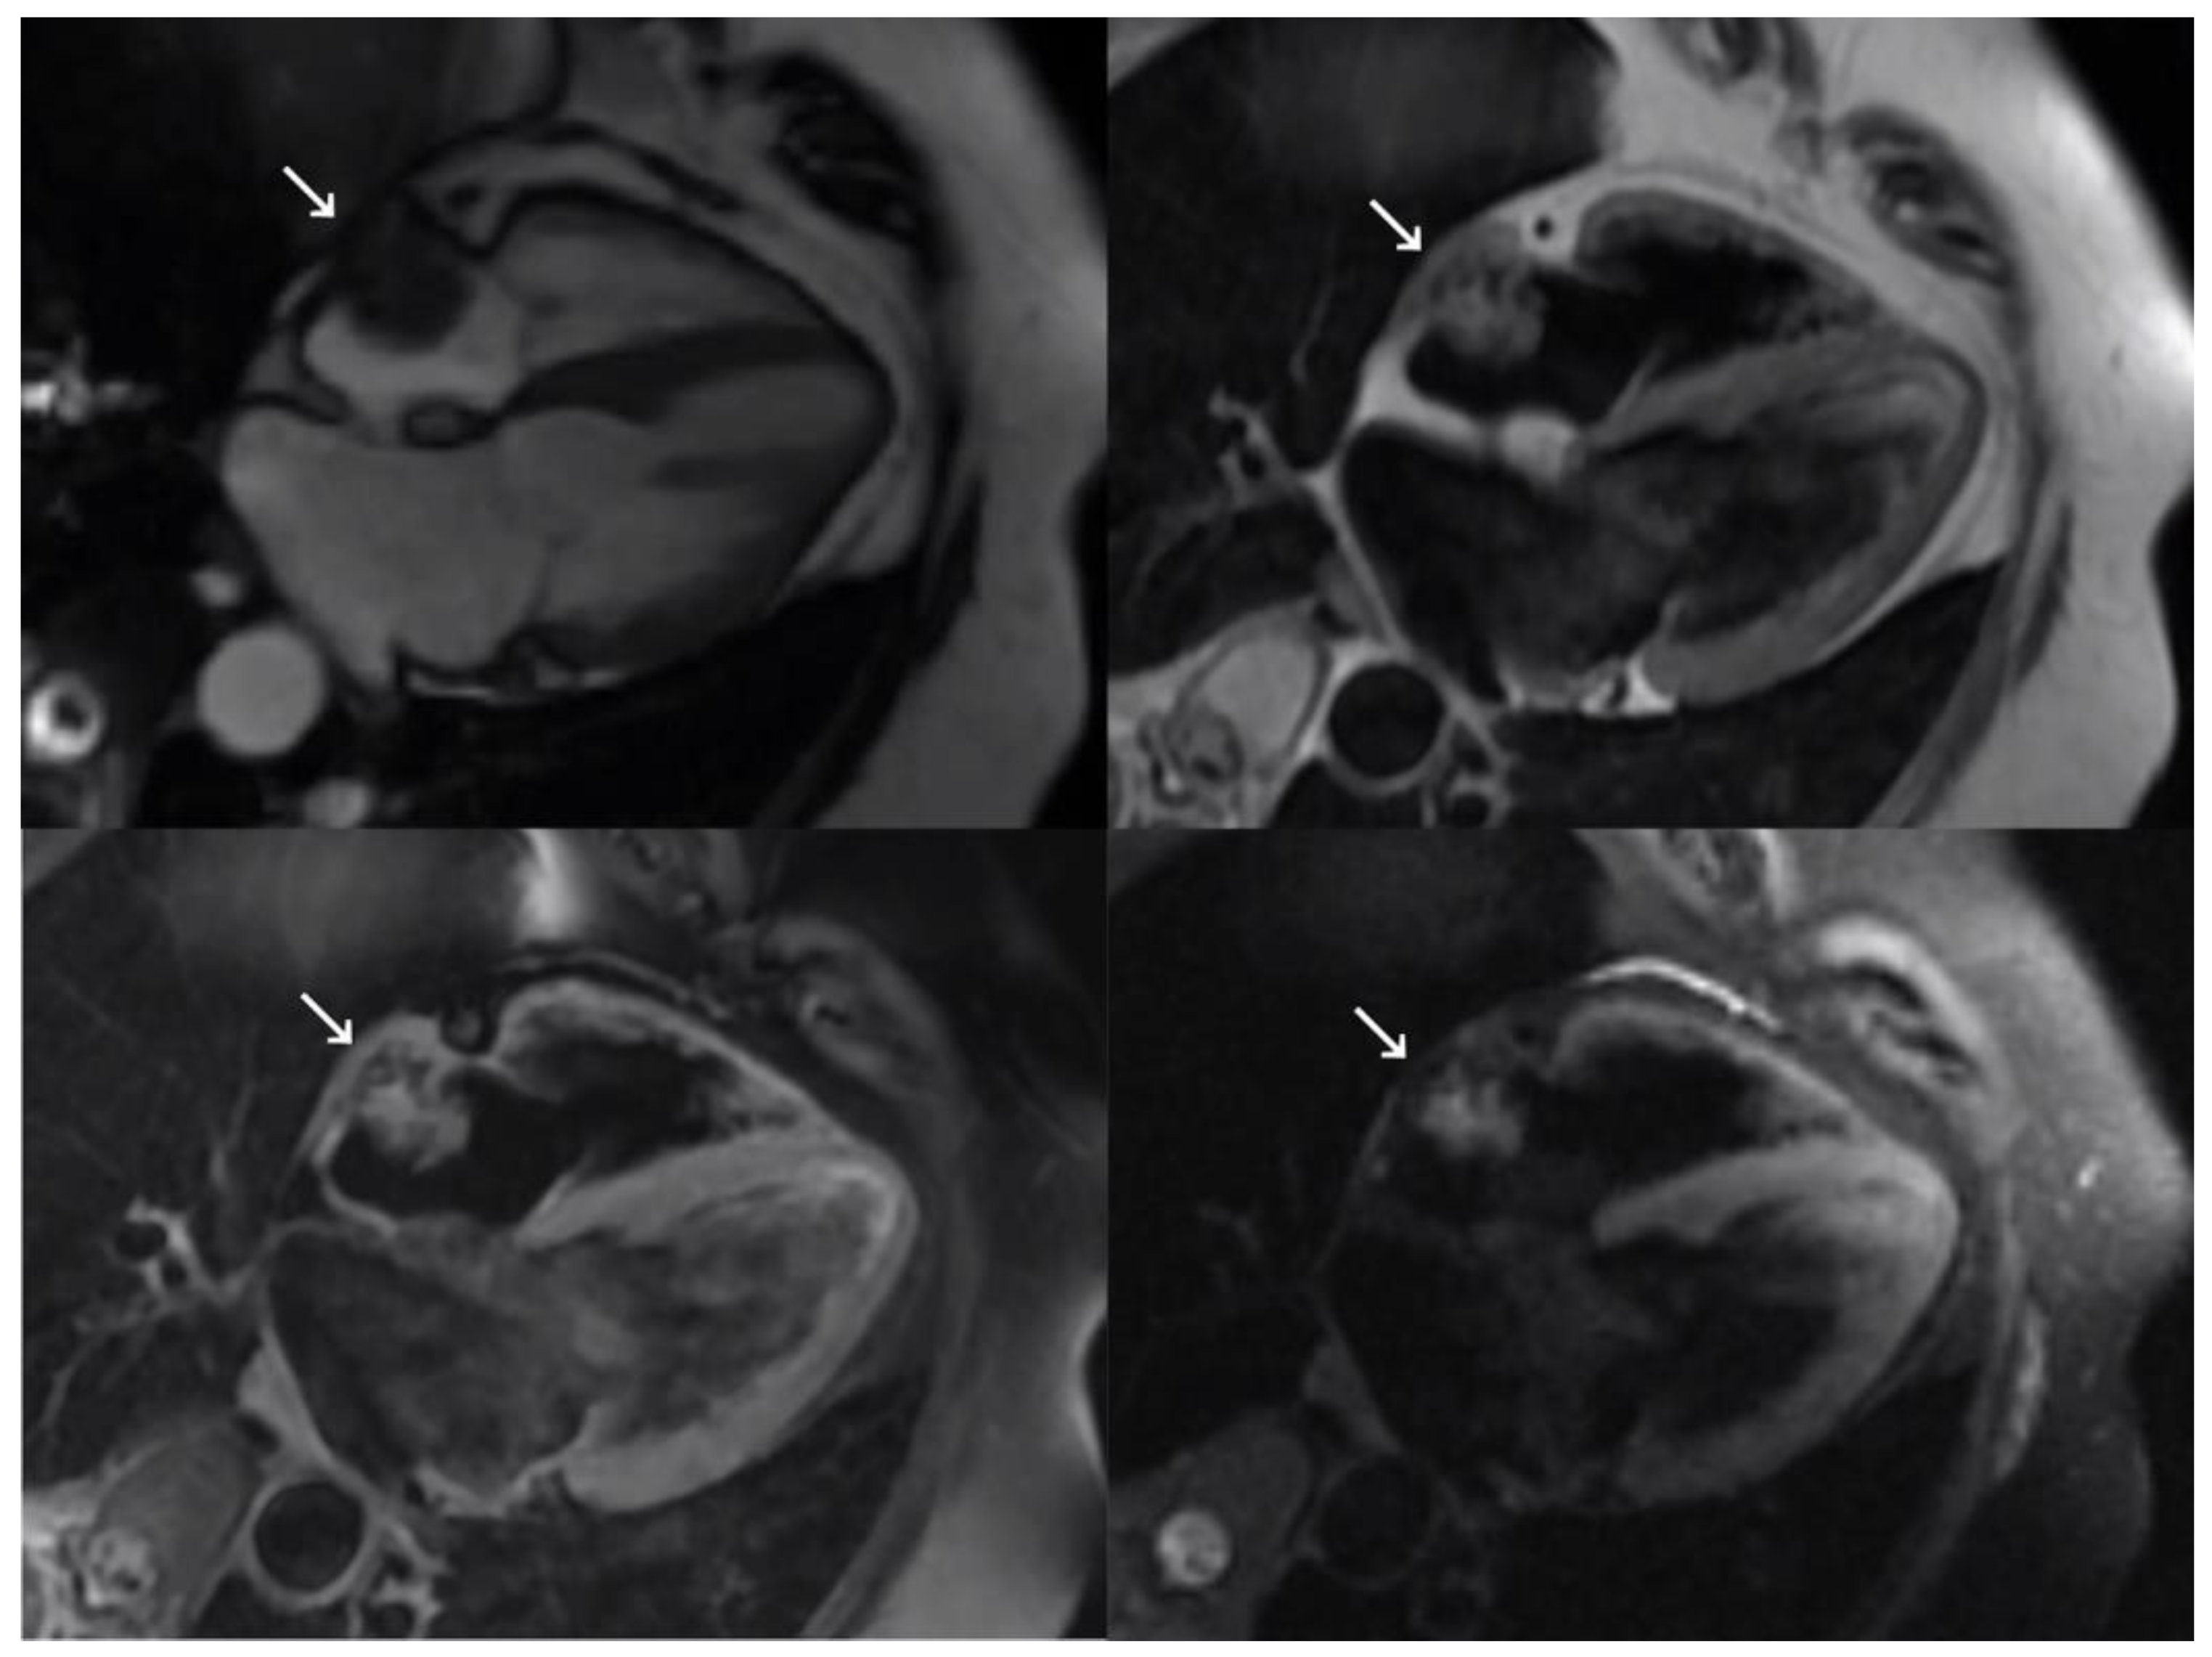

During hospitalization, TTE was performed and a 23 × 17 mm echodense mass attached to the free wall of the right atrium was detected incidentally. TEE showed a mass with a broad base of implantation that followed the movement of the atrial wall itself, independently of the central venous catheter, without protruding into the cavity or compromising the flow. These findings indicated a neoplastic origin, with a differential diagnosis of primary or metastatic tumor given the patient’s cancer history. On MRI (Figure 2), the lesion was isointense on T1 and slightly hyperintense and heterogeneous on T2 images. A discrete heterogenous associated enhancement was observed after intravenous contrast administration. The lesion had multiple small comma-shaped calcifications with doubtful infiltration of the atrial wall, suggesting a probable malignant etiology.

Figure 2. Magnetic resonance imaging showing four-chamber views of SSFP sequence (top left), double short T1 inversion recovery (IR) sequence (top right), double short T1 IR sequence (bottom left), and fat-saturated T1 triple IR sequence with contrast (bottom right). The right atrial mass is marked with a white arrow.